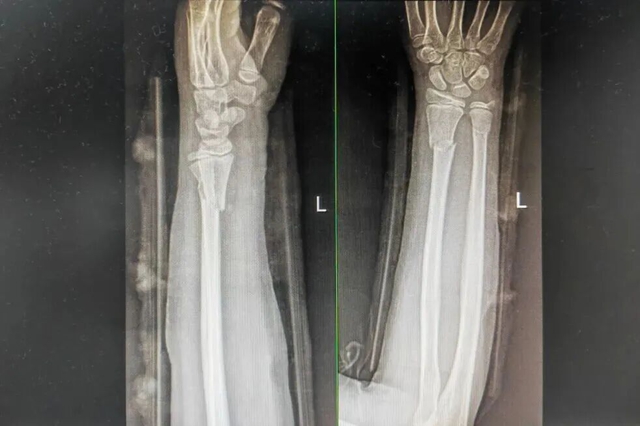

西安9岁女孩小璐(化名)玩耍时意外摔倒,导致左手前臂扭曲。紧急送医后,X光片显示其尺桡骨双骨折,断端已移位。父母带她辗转当地多家医院,均建议手术复位。

次日,一家人从西安来到医院正骨病房。此时付至江主治中医师刚结束治疗,便立刻接过病历和片子。细细比对后,他轻触小璐前臂检查,动作轻柔:“孩子骨骼柔韧,尺桡骨双骨折,首选中医正骨保守治疗……”这句话让小璐妈妈喜极而泣。

康复归来,三月余重绽舞姿